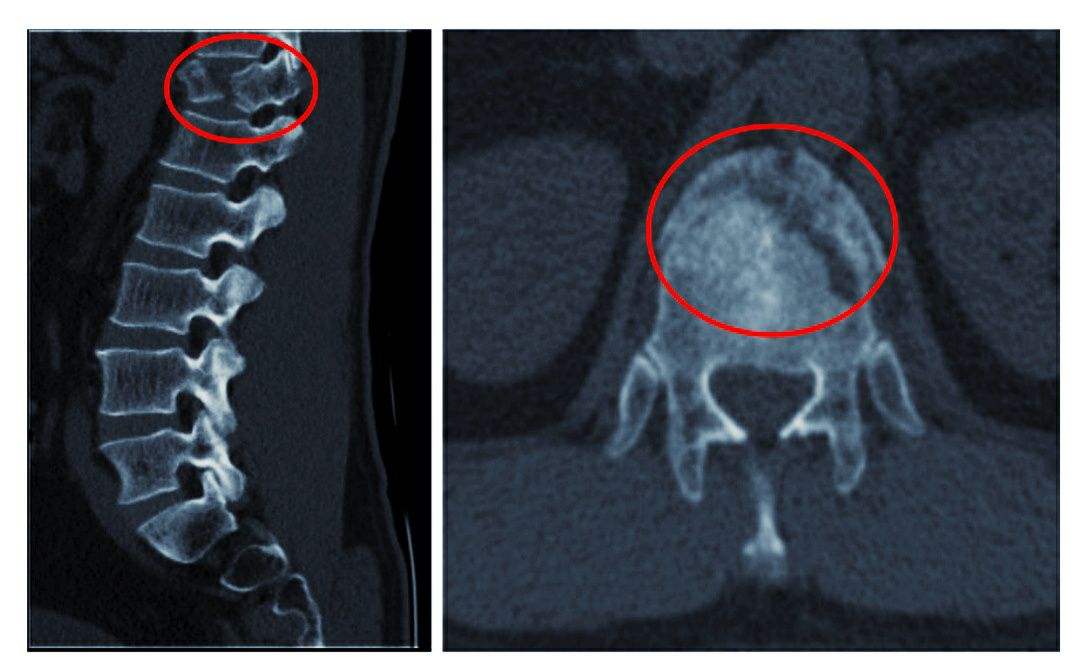

4、脊髓和神經(jīng)根的變化

因脊髓長期受壓,可出現(xiàn)脊髓變性軟化,甚至出現(xiàn)脊髓空洞,而導(dǎo)致難以恢復(fù)的損傷。其原因主要有血運(yùn)障礙,椎管縱徑縮短,骨贅或椎間盤組織等混合突出物的直接壓迫脊髓。神經(jīng)根因長期受壓而發(fā)生變性反應(yīng),出現(xiàn)肢體麻木及運(yùn)動障礙。